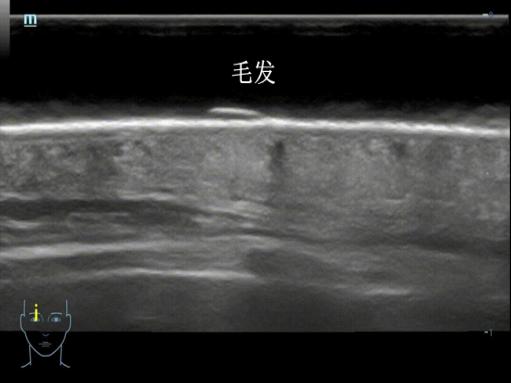

我们的皮肤从外到内分为表皮、真皮、皮下组织三层,就像一层薄外套裹着两层“保暖层”。在超高频探头下,薄薄的皮肤可以变成一张 “皮肤剖面图” ,不仅可以看到表皮、真皮、皮下组织的结构,精确测量其厚度,还可以清晰显示其内的毛发、毛囊、皮脂腺等肉眼及普通超声无法识别的结构。

脱发评估

超高频超声可以显示头皮毛囊密度及毛囊状态,正常人的毛囊密集、排列整齐,脂溢性脱发患者毛囊间距增宽,斑秃显示毛囊稀疏、排列杂乱。超高频超声可以为治疗选择、疗效评估及随访监测提供量化工具。